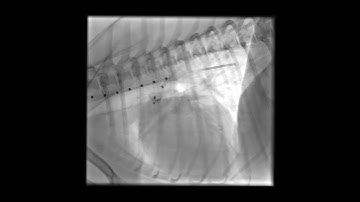

PDA Coil Closure Post coil closure aortogram